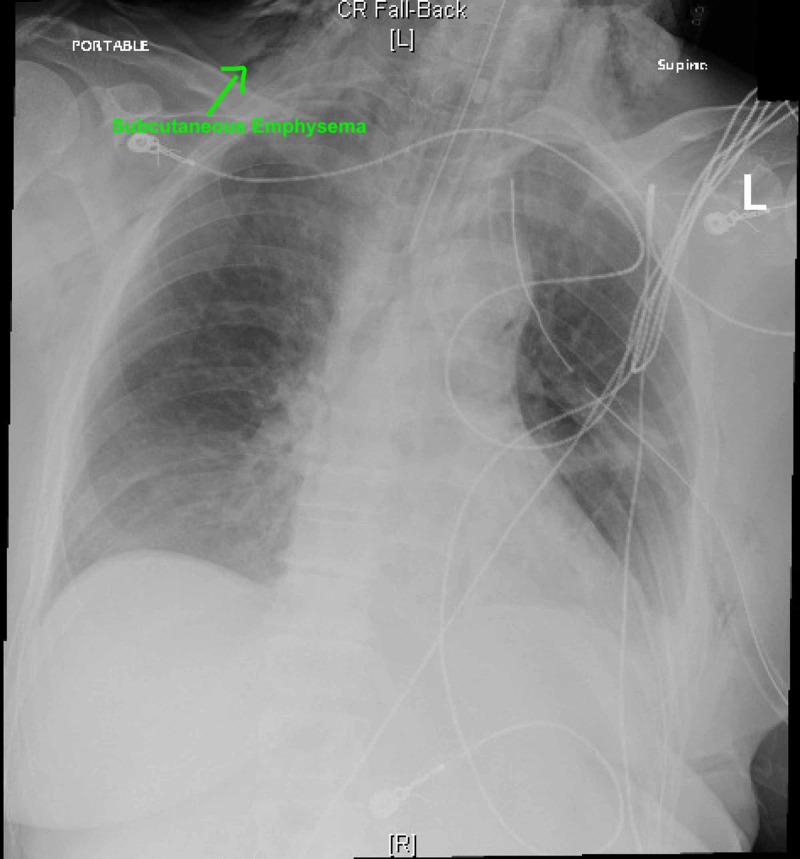

The authors present a case of a patient who used Kambo frog poison for body cleansing that induced severe vomiting and led to esophageal rupture followed by tension pneumothorax and septic shock. Kambo is the waxy substance secreted by the nocturnal giant tree frog . Kambo, which is poisonous, is commonly believed in South America to have cleansing and healing properties. As alternative medicine becomes more common, and as more tourists frequent our hospitals, knowledge of these types of ritual related exposures is important for the practicing emergency physician to be aware of.

作者报告了一例患者,该患者使用坎波蛙毒进行身体清洁,引发了严重呕吐,导致食管破裂,随后出现张力性气胸和感染性休克。坎波是夜行性巨树蛙分泌的蜡状物质。坎波有毒,在南美洲通常被认为具有清洁和治疗功效。随着替代医学越来越普遍,以及越来越多游客前往我们的医院就诊,了解这些与仪式相关的接触类型对于执业急诊医生来说非常重要。